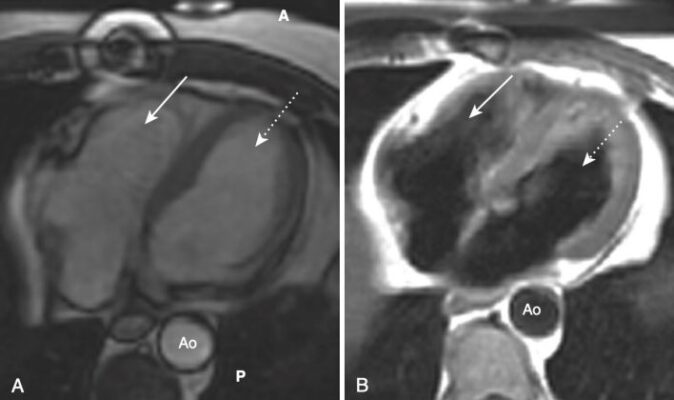

- MRI tim có thể mô tả sẹo do nhồi máu cơ tim, tràn dịch màng tim, các khiếm khuyết giải phẫu hoặc khối và có thể đánh giá chức năng của van và buồng tim.

- Một trong những lợi ích của MRI là hình ảnh của nó có thể được hiển thị ở bất kỳ mặt phẳng nào. Bên cạnh các mặt phẳng cắt ngang (axial), đứng dọc (sagittal) và đứng bên (coronal, trán), có một số góc nhìn đặc hiệu thường được sử dụng trong MRI tim cho phép hình dung rõ nhất về tim. Chúng được gọi là trục dài cắt ngang (còn được gọi là mặt cắt bốn buồng), trục dài thẳng đứng, trục ngắn và mặt cắt ba buồng.

- Cấu trúc giải phẫu của tim trong các mặt phẳng cắt ngang, đứng dọc và trán giống như được thấy trên CT (Hình 16).

- Tùy thuộc vào chuỗi xung MRI được sử dụng để thu được hình ảnh, máu có thể được mô tả là đen (thường sử dụng một xung gọi là chuỗi xung spin echo) và thường được sử dụng để đánh giá giải phẫu, hoặc sáng, nghĩa là màu trắng (thường sử dụng một chuỗi xung gọi là chuỗi xung echo gradient), và thường được sử dụng nhất để đánh giá chức năng (Hình 21).